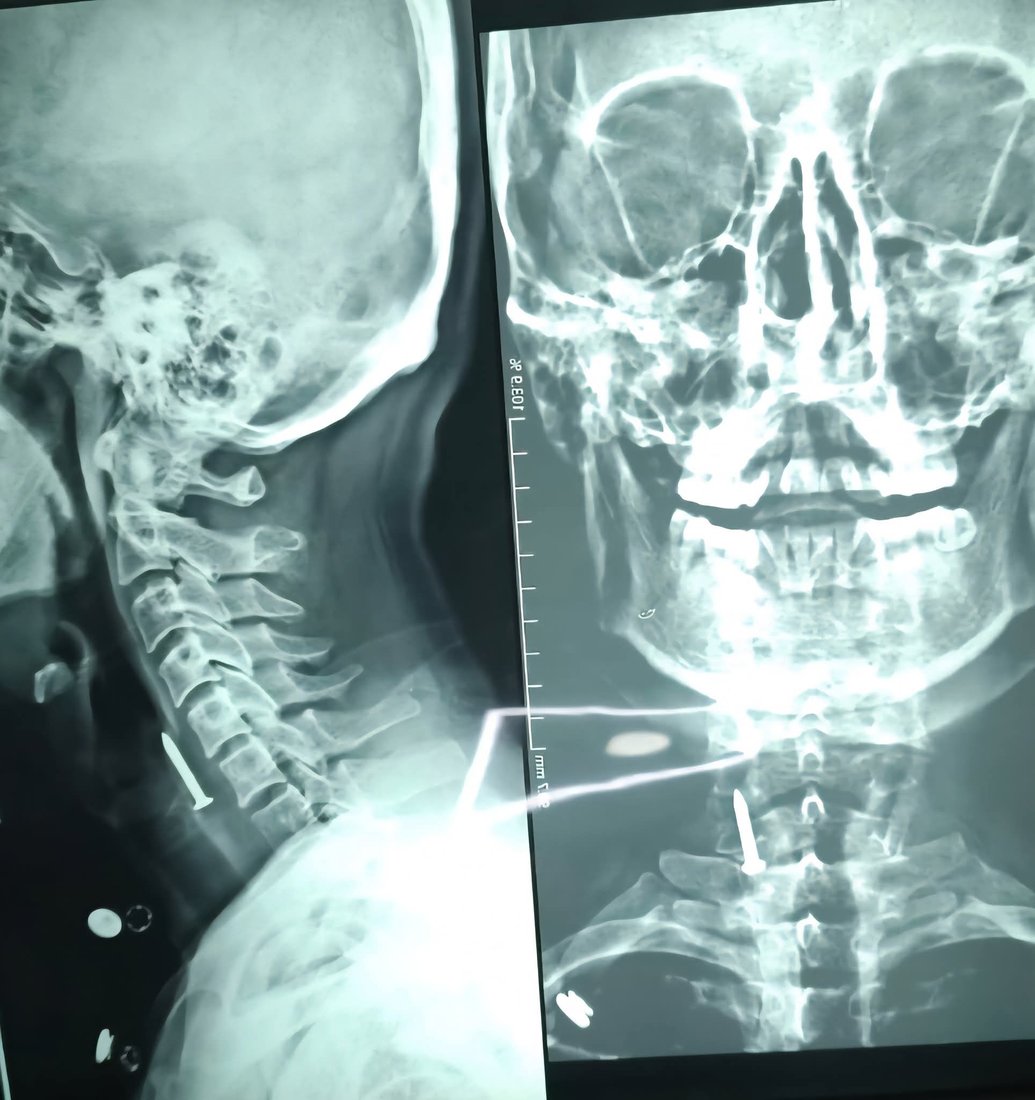

لە سلێمانی بزمارێک لە گەڕوی هاوڵاتییەکی تەمەن 36 ساڵدا دەرهێنرا.

بەڕێوەبەرایەتی گشتی تەندروستی سلێمانی بڵاویکردووە، لەلایەن تیمی ئێشکگری نەخۆشخانەی كۆئەندامی هەرس و جگەری فێرکاری، بزمارێک لە گەروی چارەخوازێکی تەمەن 36 ساڵدا دەرهێنراوە.

تەندروستی سلێمانی هیچ ئاماژەیەکی بە چۆنیەتی و هۆکاری قوتدانی ئەو بزمارە لەلایەن ئەو هاوڵاتییەوە نەکردووە.